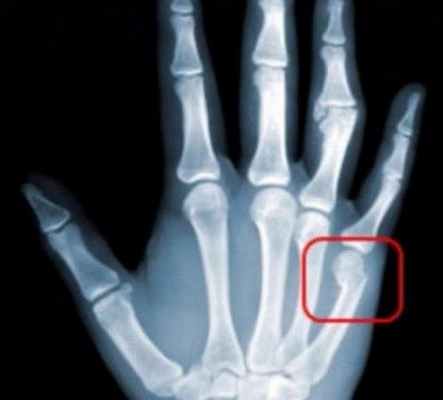

Переломы пястных костей и пальцев кисти.

Переломы костей кисти являются следствием травматического воздействия

Оперативное лечение выполняется при невозможности устранить имеющееся смещение отломков, а так же при нестабильных формах переломов, когда отломки невозможно удержать в правильном положении в гипсовой повязке.

При отсутствии соответствующего лечения кость срастается со смещением отломков, часто формируются несращения, что приводит к появлению деформации кисти и стойкому нарушению ее функции.

Использование в работе интраоперационного рентгенологического контроля позволяет проводить малотравматические оперативные вмешательства, что обеспечивает условия для ранней функциональной реабилитации.

Лечение выбирается в зависимости от типа перелома (без смещения, со смещением отломков, сочетанные с повреждениями других структур кисти, множественные и др.). Это различные виды современного остеосинтеза костей (спицами, винтами, накостными пластинами).